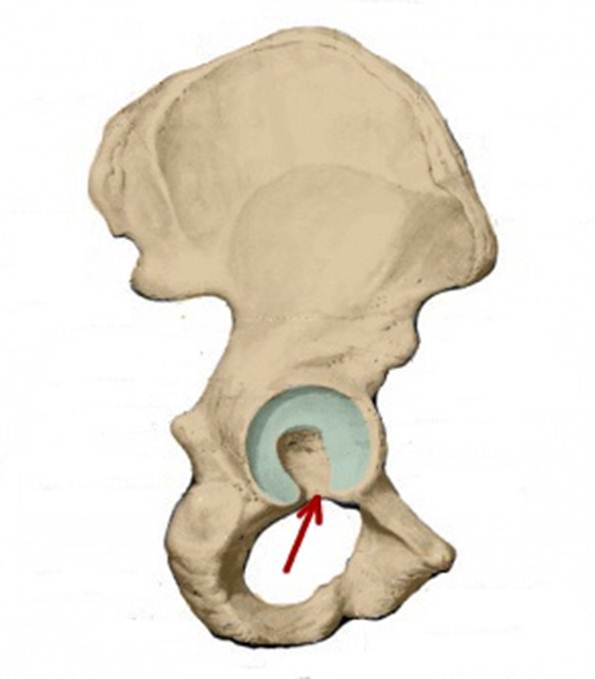

S: Стрелка указывает на facies lunata (латинский язык).

S: Стрелка указывает на incisura acetabuli

S: Стрелка указывает на labrum acetabuli

S: Стрелка указывает на lig. Capitis femoris

S: Стрелка указывает на facies lunata